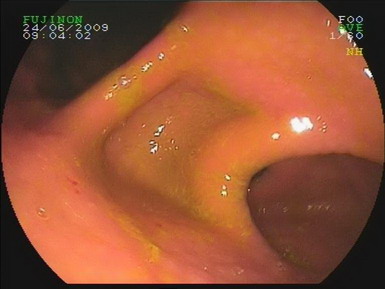

2009.6.24胃镜:

慢性浅表性胃炎,十二指肠淤滞症原因待查,肠系膜上动脉压迫综合症?(胃内可见胆汁样物反流,十二指肠球扩张,降部明显扩张,水平部远端似可见狭窄,持续充气肠腔不能打开。)